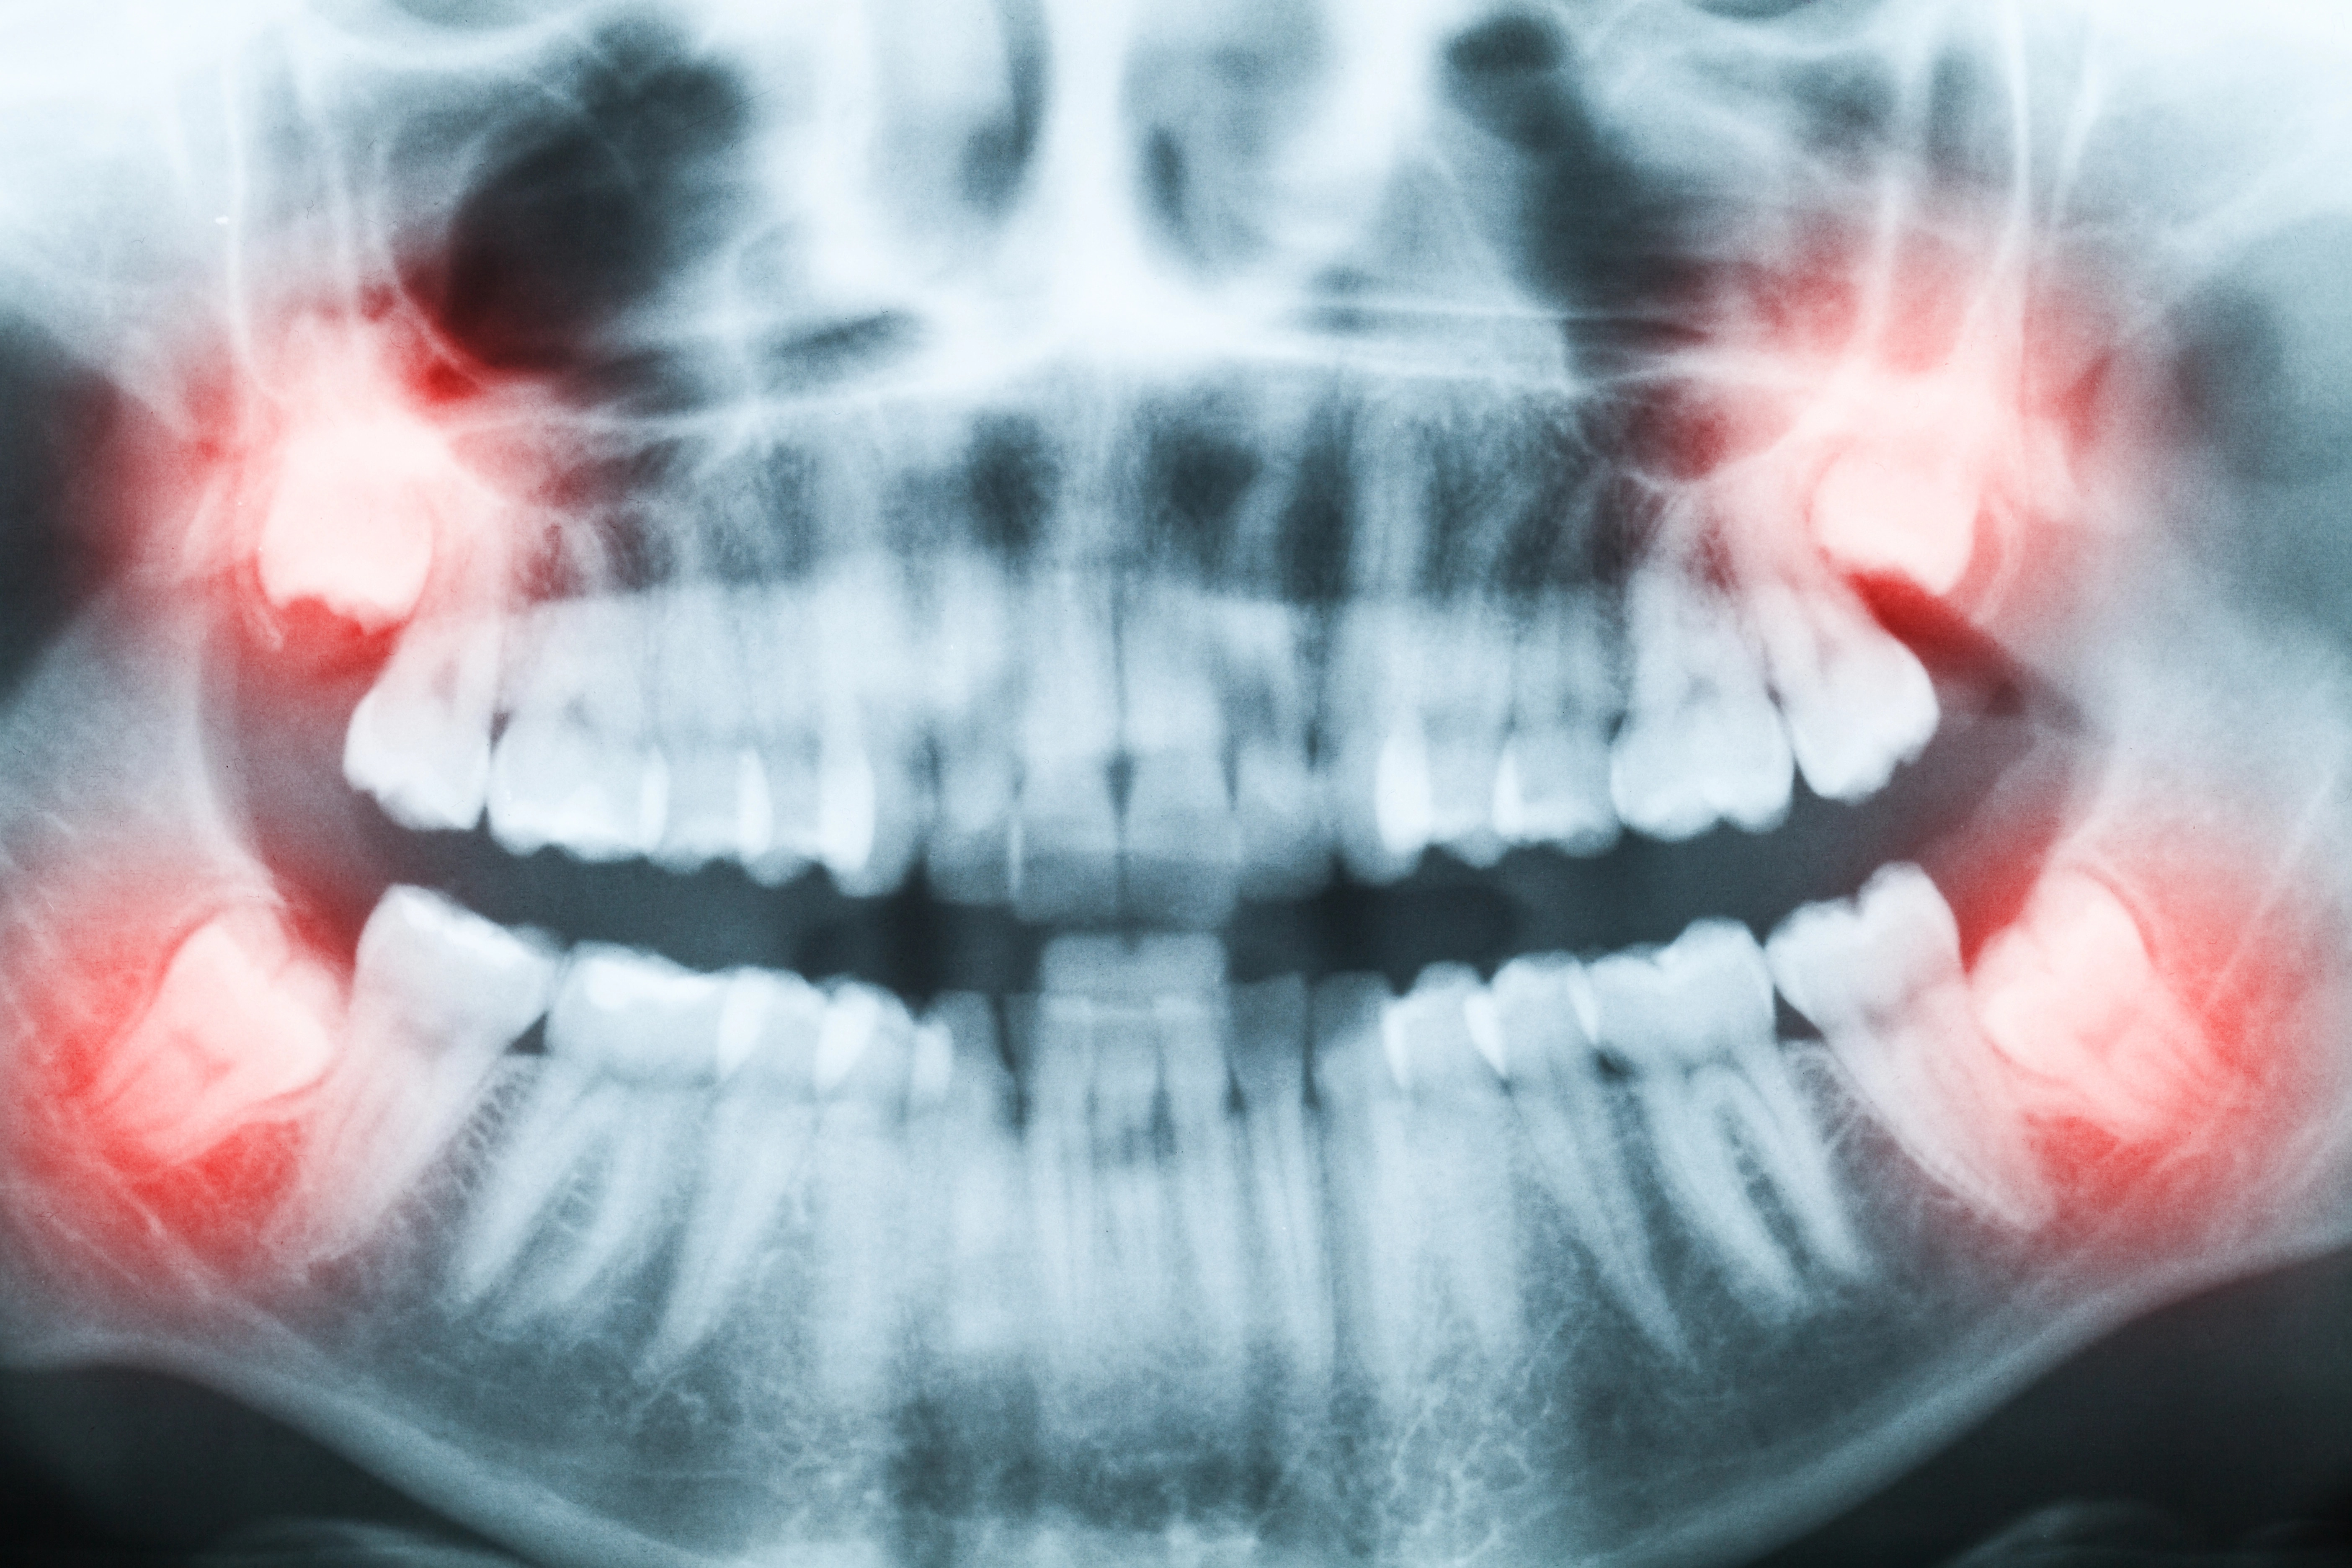

Read MoreHow to Know When It’s Time to Get Your Wisdom Teeth Out

Wisdom teeth are the third molars, typically appearing between the ages of 15 and 25. Not everyone needs them removed, but many do. If you’ve noticed pain in the back of your mouth, tenderness, swelling, or even a new tooth poking through your gums, you may be wondering how to know when it’s time to […]